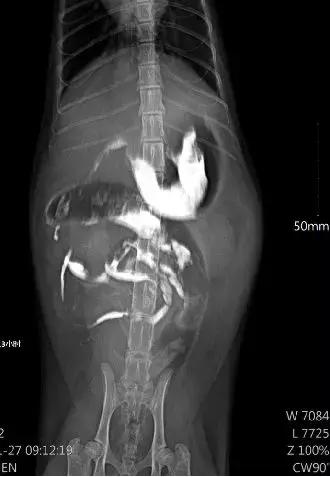

通过血常规、生化、DR钡餐、FCoV等检查

发现猫咪身体多项数据异常

钡餐未正常下流,13小时仍大部分在胃区

冠状病毒PCR检测呈阳性

结合各项指标、临床症状、腹腔检查

猫咪疾病被诊断为猫传染性腹膜炎

1、开腹探查、腹腔清洗

发现腹水,网膜、腹膜、肝、肾、脾脏、肠道的浆膜面出现纤维蛋白沉积及脓性肉芽肿

进行腹腔清洗后

后再无产生腹水,只有胀气